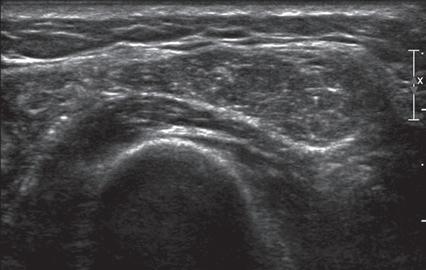

1.22 Tissue Harmonic Imaging. Ultrasound images of a recurrent giant cell tumor (arrowheads) without (A) and with (B) tissue harmonic imaging show increased definition of the mass borders in B. Note posterior increased through-transmission.

FIGURE 1.23 Tissue Harmonic Imaging. Ultrasound images of full-thickness supraspinatus tendon tear in long axis (arrows) without (A) and with (B) tissue harmonic imaging show clearer distinction of retracted tendon stump (left arrow) because intervening fluid is more hypoechoic.